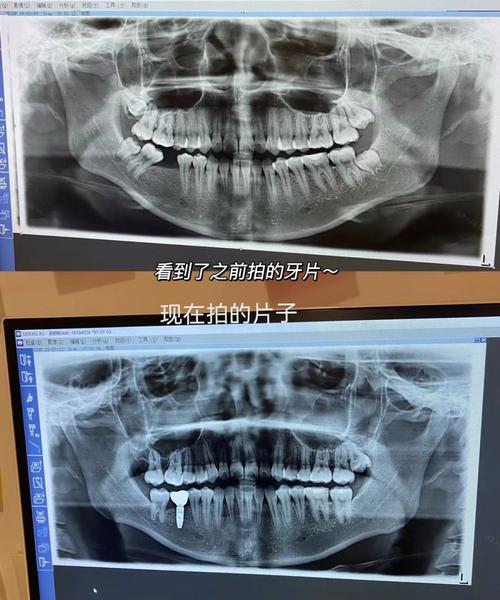

Q1:牙片CT和普通牙片(根尖片、曲面断层片)有什么区别?

A:牙片CT是三维影像,可多角度、多层面显示颌骨内部结构(如下颌神经管、根尖病变三维范围),分辨率高(可达0.1mm),尤其适用于复杂病例(如种植术前评估、根管治疗疑难根管);普通牙片是二维影像,存在结构重叠(如上颌窦与牙根重叠),分辨率较低,但辐射剂量更小,价格更低,适用于常规检查。